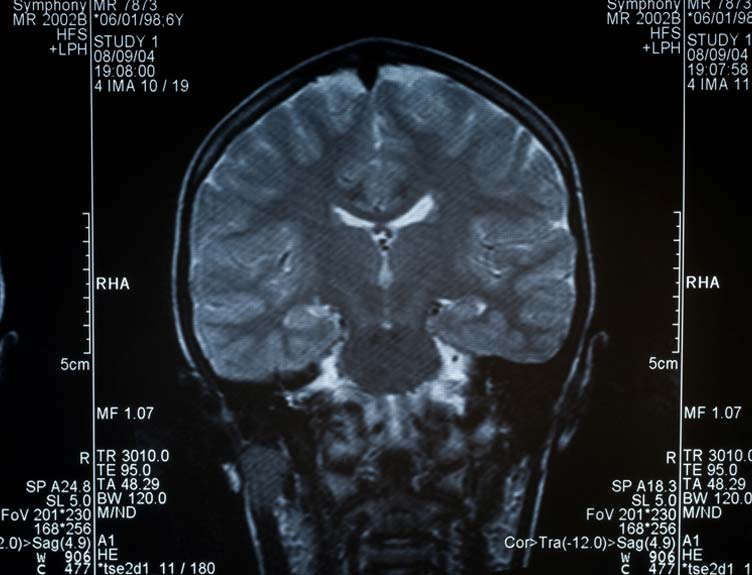

Conducted by the global ENIGMA-Epilepsy consortium, the study extracted structural brain measures MRI brain scans of 2,149 people with epilepsy, and compared with 1,727 healthy controls.

The team found reduced grey matter thickness in parts of the brain's outer layer (cortex) and reduced volume in subcortical brain regions in all epilepsy groups when compared to the control group. Reduced volume and thickness were associated with longer duration of epilepsy. Notably, people with epilepsy exhibited lower volume in the right thalamus - a region which relays sensory and motor signals, and has previously only been associated with certain epilepsies - and reduced thickness in the motor cortex, which controls the body's movement.